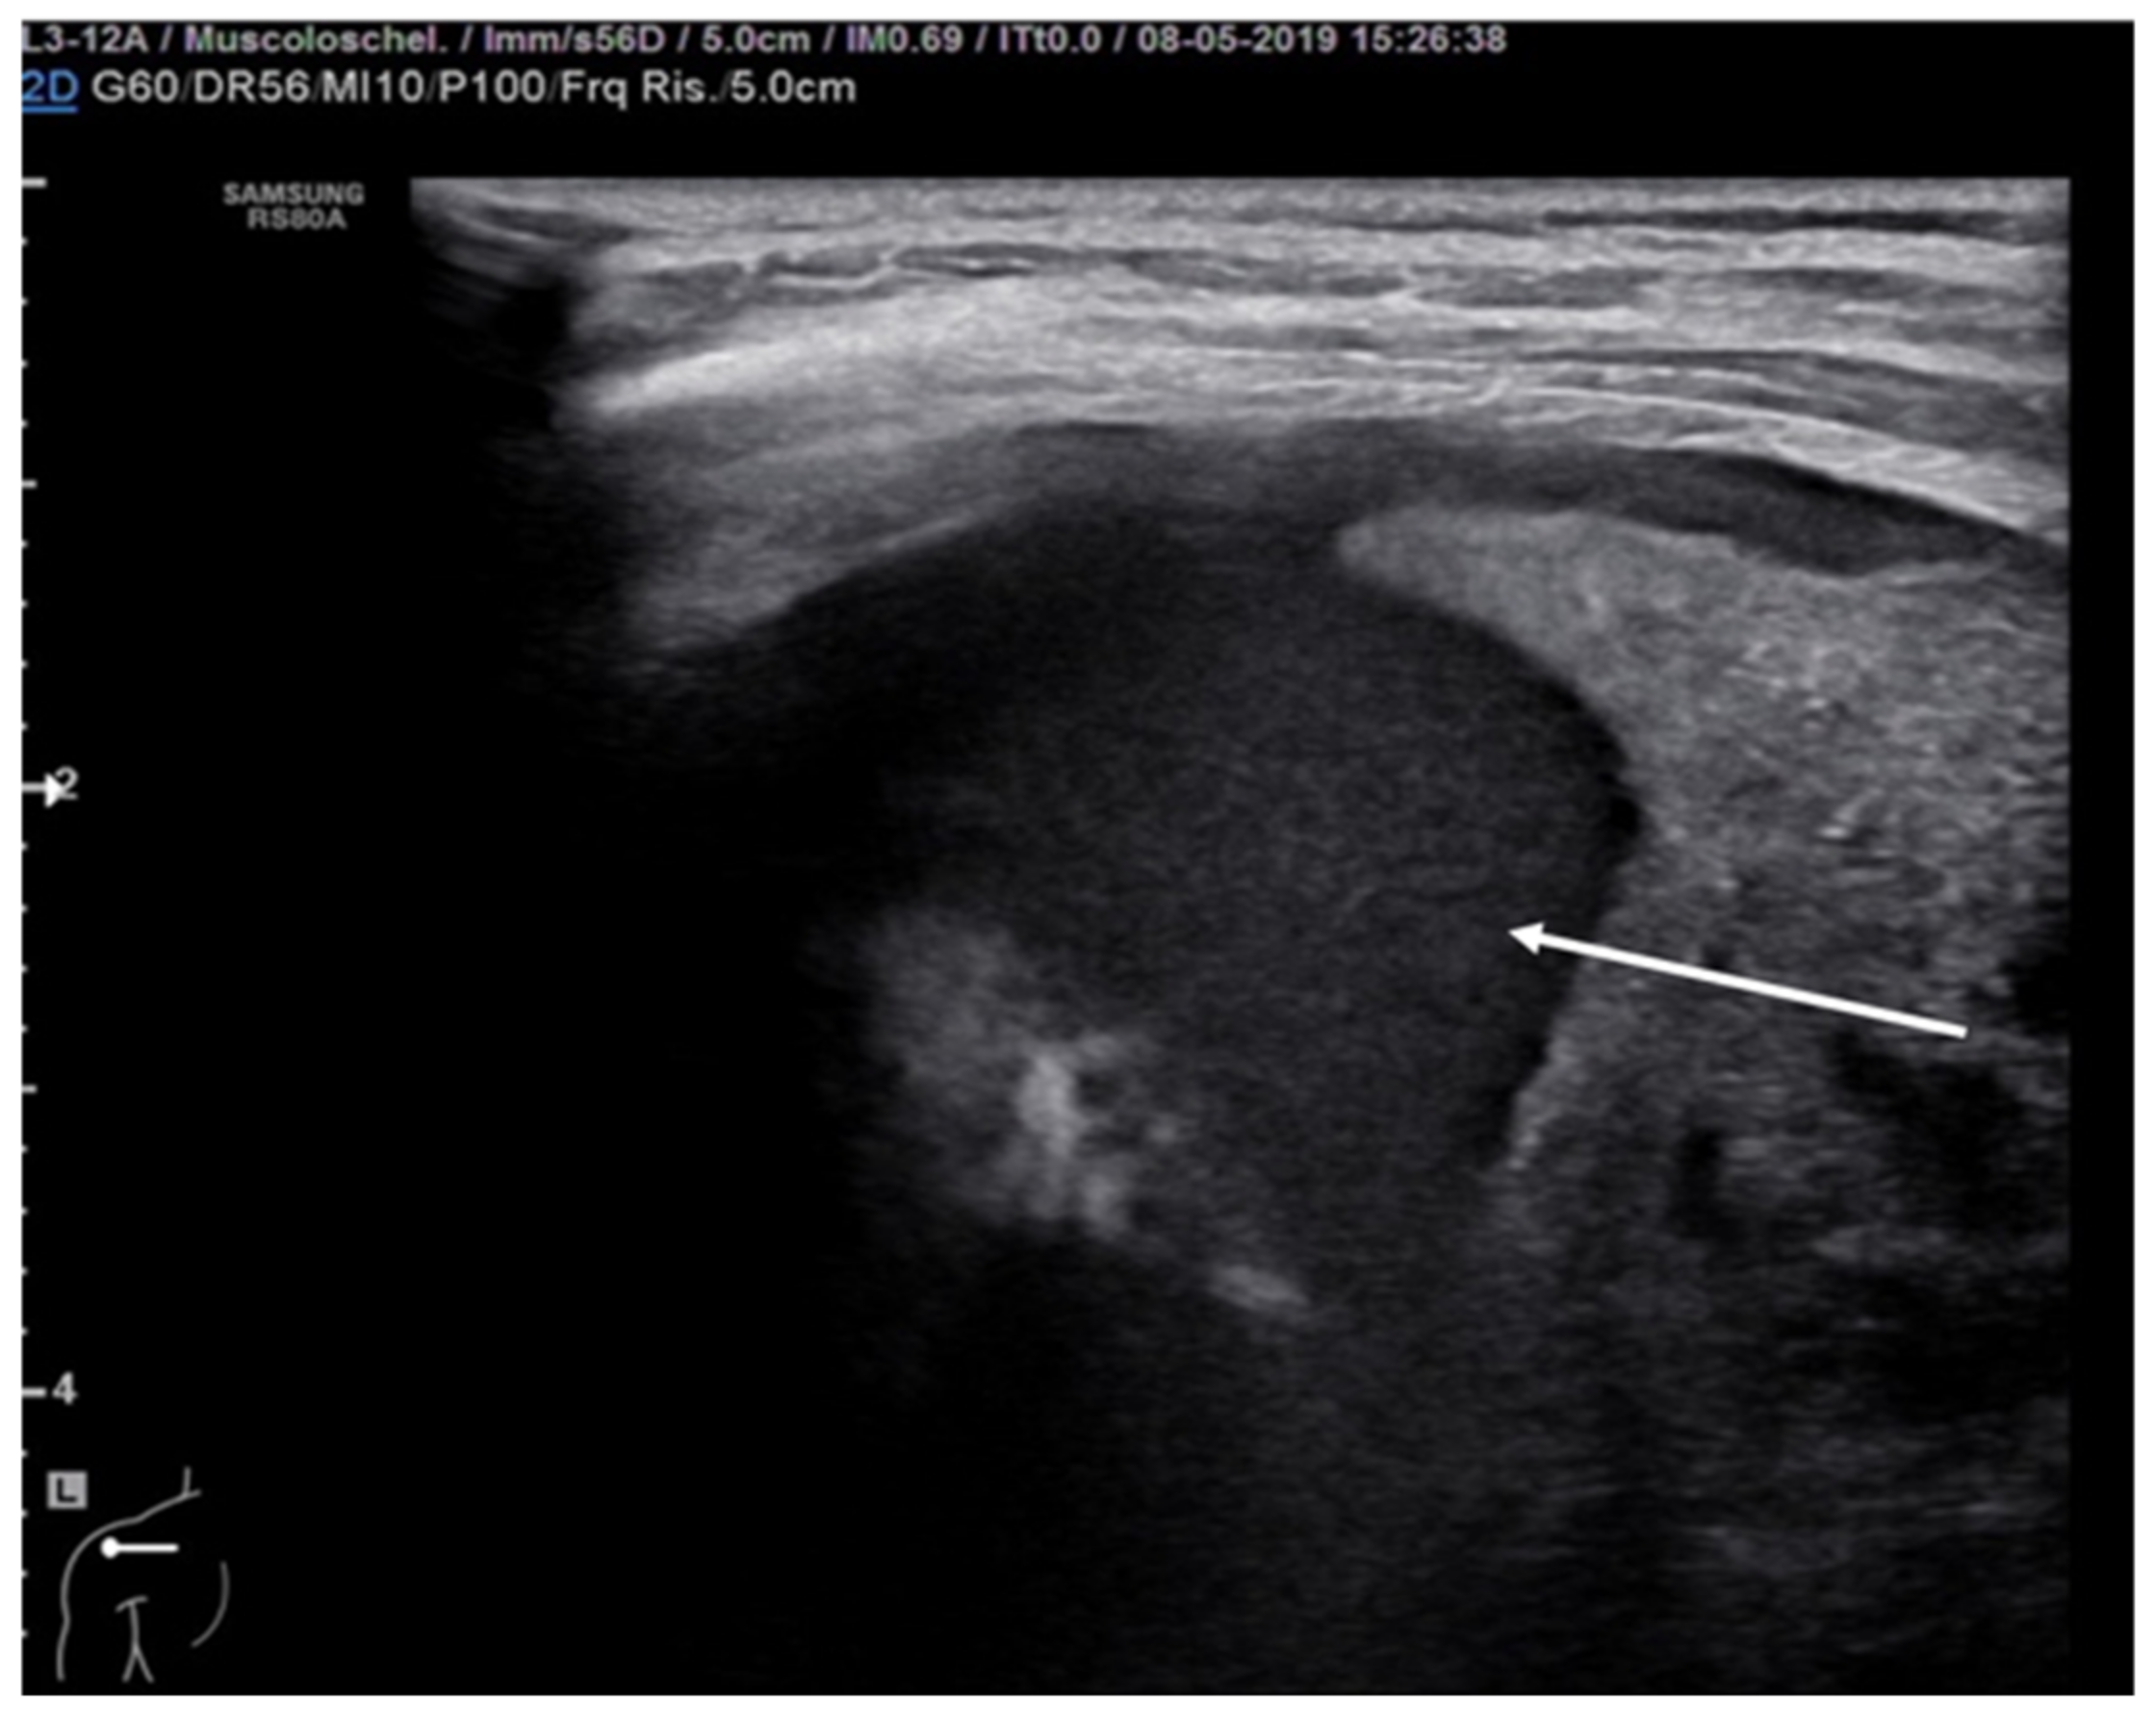

8. Pneumothorax, Pleural Effusion Empyema and Lung Abscess

- Kraft, C.; Lasure, B.; Sharon, M.; Patel, P.; Minardi, J. Pediatric Lung Abscess Immediate Diagnosis by Point-of-Care Ultrasound. Pediatr. Emerg. Care 2018, 34, 447–449. [Google Scholar] [CrossRef]

- Lin, F.; Chou, C.; Chang, S. Differentiating pyopneumothorax and peripheral lung abscess: Chest ultrasonography. Am. J. Med. Sci. 2004, 327, 330–335. [Google Scholar] [CrossRef]

- Calder, A.; Owens, C.M. Imaging of parapneumonic pleural effusions and empyema in children. Pediatr. Radiol. 2009, 39, 527–537. [Google Scholar] [CrossRef]

- Chen, H.J.; Yu, Y.H.; Tu, C.Y.; Chen, C.H.; Hsia, T.C.; Tsai, K.D.; Shih, C.M.; Hsu, W.H. Ultrasound in peripheral pulmonary air-fluid lesions. Color doppler imaging as an aid in differentiating empyema and abscess. Chest 2009, 135, 1426–1432. [Google Scholar] [CrossRef] [PubMed] [Green Version]

- De Benedictis, F.; Kerem, E.; Chang, A.B.; Colin, A.A.; Zar, H.J.; Bush, A. Complicated pneumonia in children. Lancet 2020, 396, 786–798. [Google Scholar] [CrossRef]